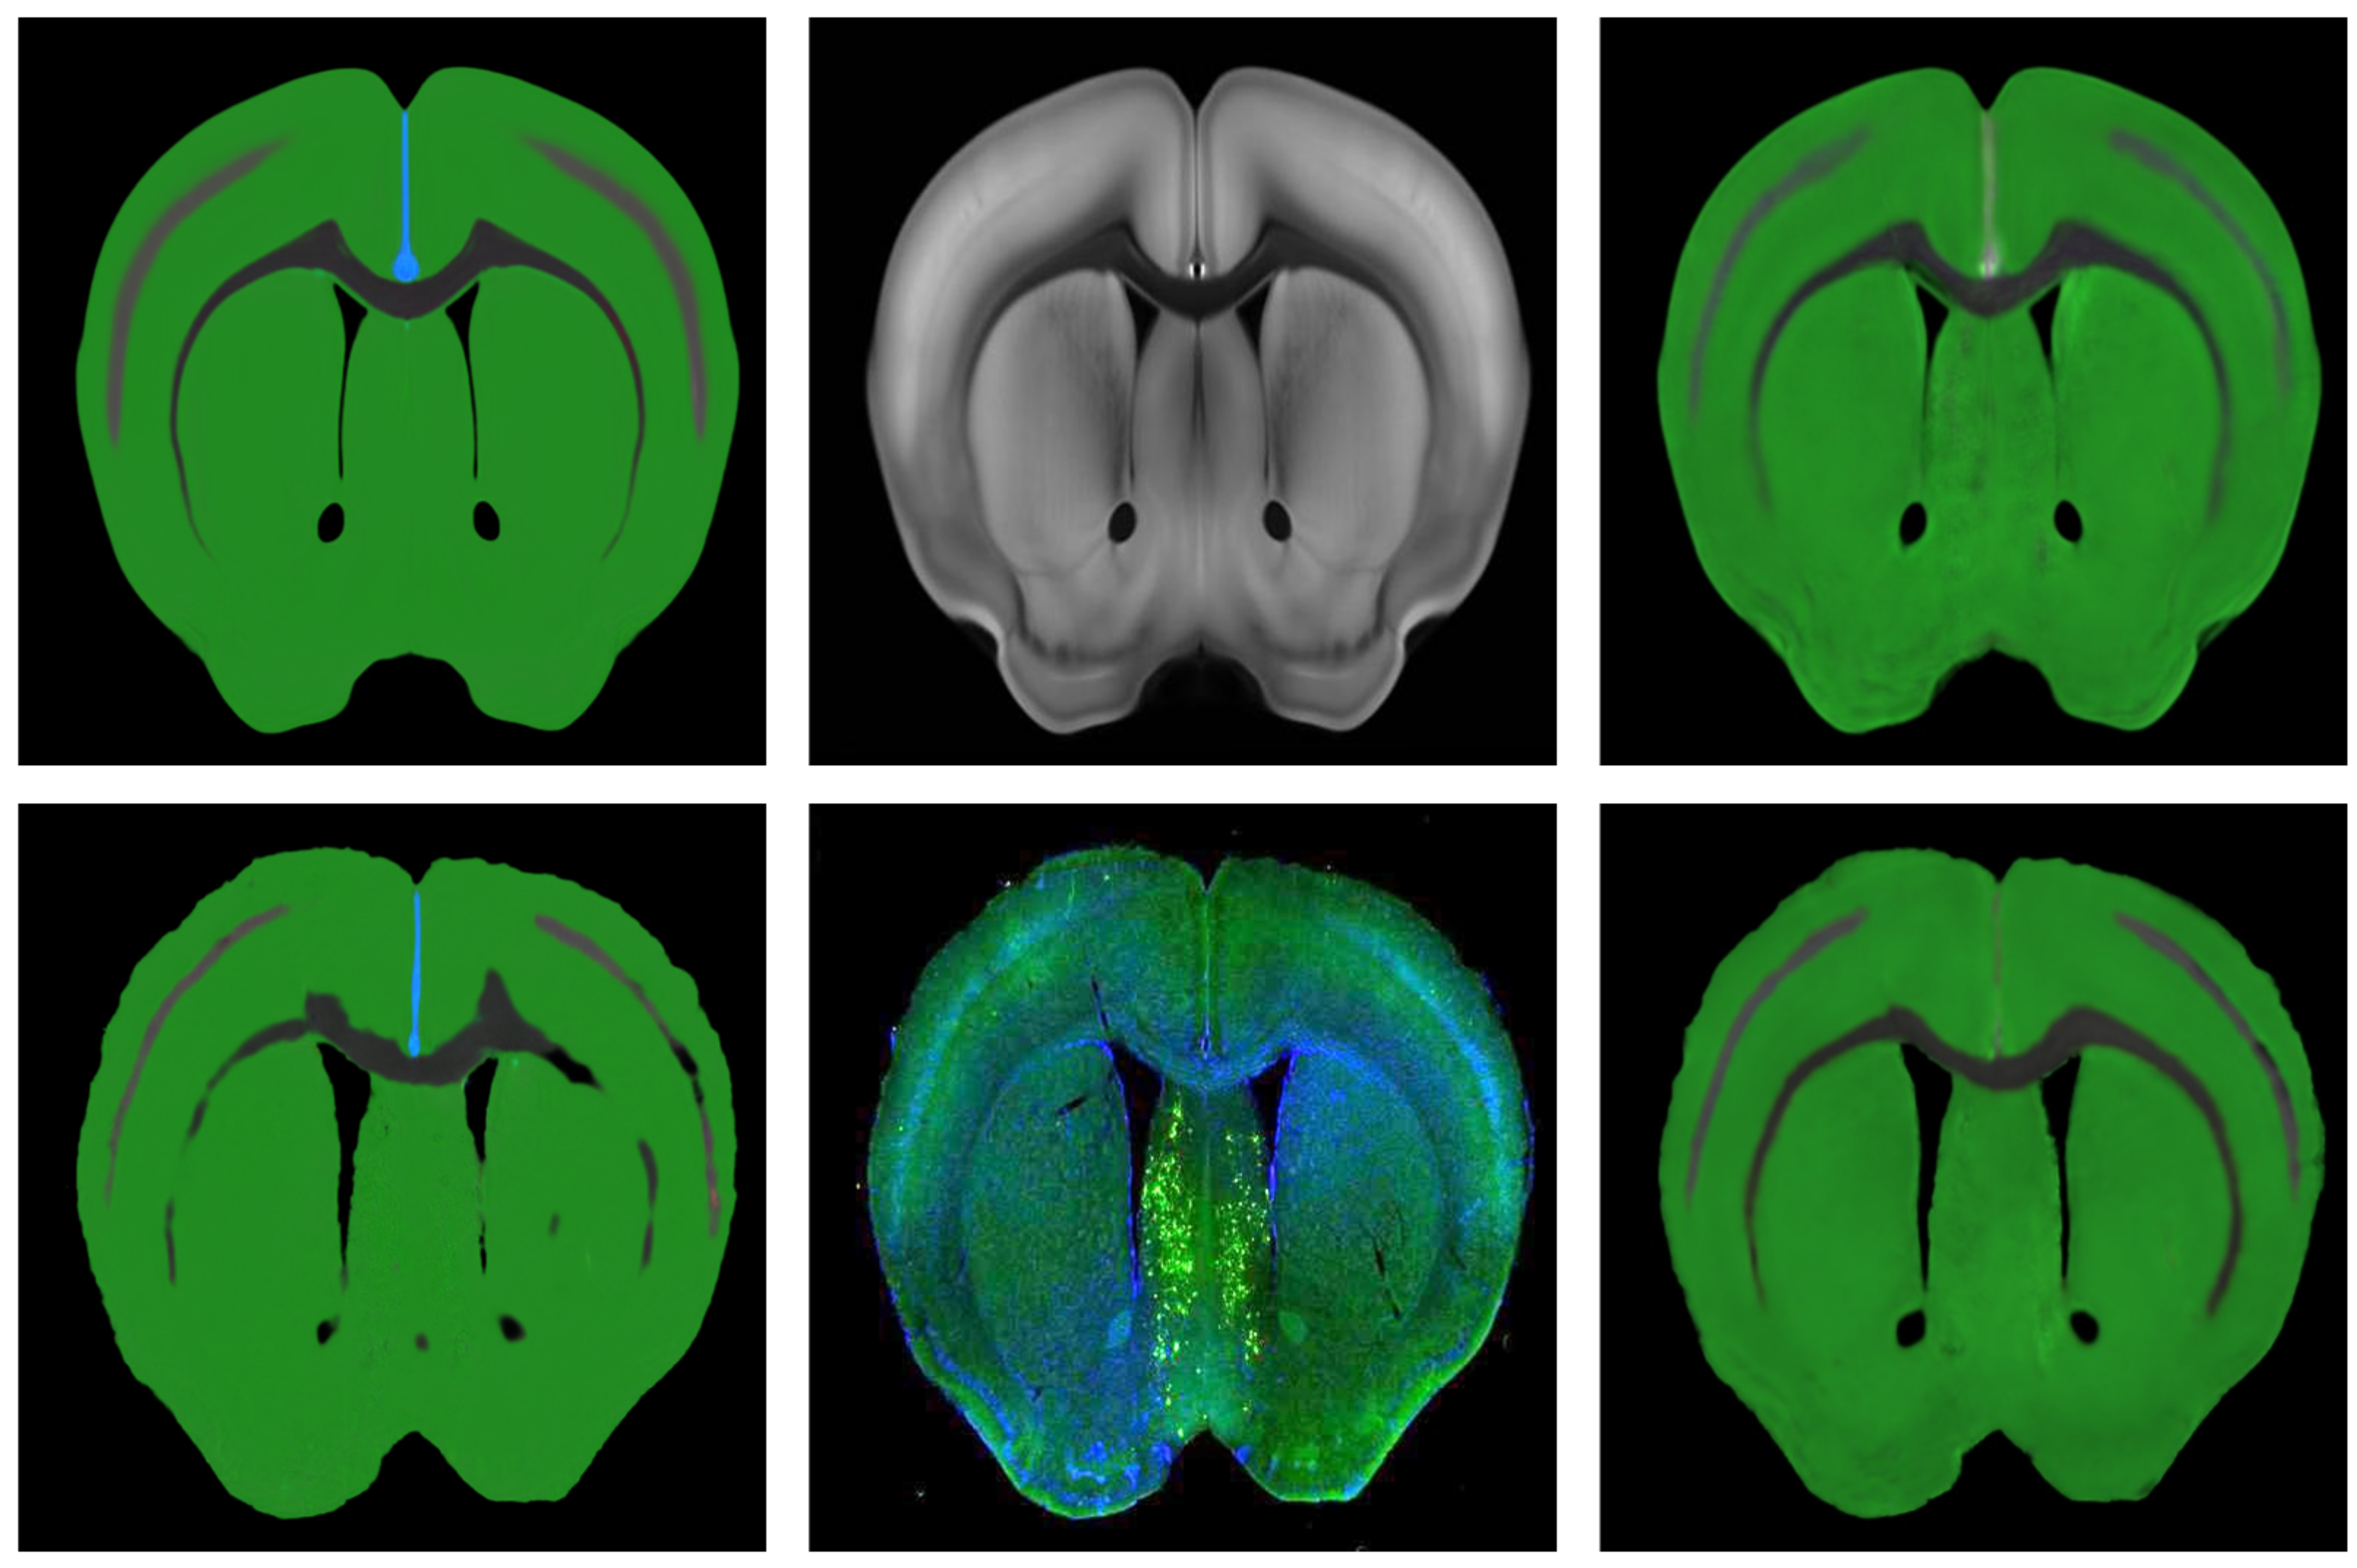

3.4. Performance Evaluation

After the optimal spatial deformation field is obtained, the spatial transformation layer can be used to apply the spatial deformation field to the ADA to evaluate the performance of the registration results. The ADA has rich regional division information, and different brain regions are separated by different colors. Thus, the edges of regions can be easily extracted, and then the edges of the regions are fused with the brain slices to complete the localization of the regions in the mouse brain slices. The performance of different methods was compared with the accuracy of localization, and the results are shown in Figure 5.

Figure 5. Regional localization result after image fusion.